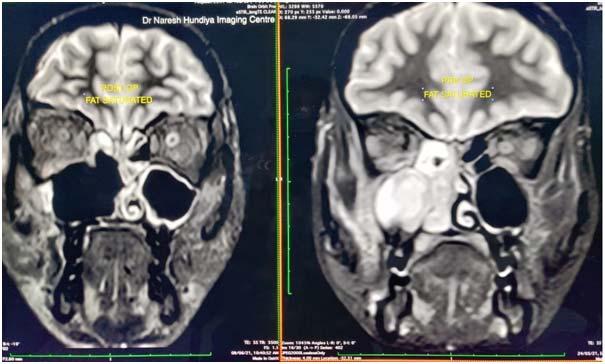

Routine blood investigations, ECG, chest Xray, CT scan and MRI of the face (including orbits) and brain were done (Fig 1).

Fig 1 — Pre-operative and Postoperative coronal MRI slice